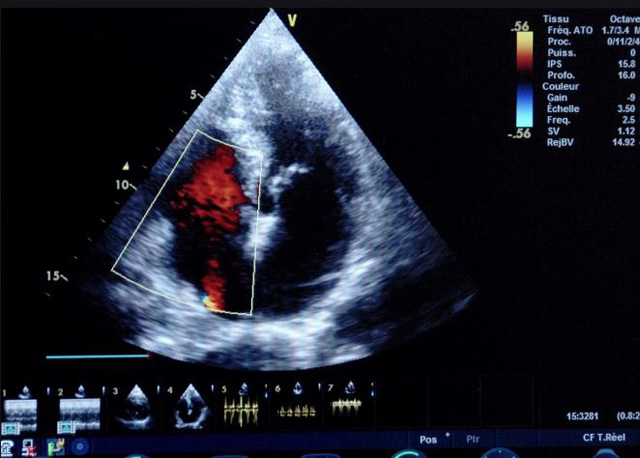

二、彩色室壁運(yùn)動分析

(一)基本原理彩色室璧運(yùn)動分析,從整體散射數(shù)據(jù)中識別心內(nèi)膜邊界,并與前一幀彩色不同,心臟收縮或舒張期開始到結(jié)束時心內(nèi)膜的全部過程。每一次順序顯示結(jié)束后,原來的彩色自動消失,以便進(jìn)入下一個顯示過程。其結(jié)果是獲得對應(yīng)于每一個心動周期的彩色顯示,描繪特定周期內(nèi)室壁運(yùn)動的時間運(yùn)動軌跡。

(二)操作步驟根據(jù)背向散射數(shù)據(jù)中將心內(nèi)膜運(yùn)動的位移過程分類為組織或血液的原理,邊緣檢測跟蹤心內(nèi)膜和血液的界面。橙色表示收縮期的開始,收縮期不同時相逐幀顯示色彩均疊加在收縮末期最后一幀圖像中。檢查時,可按以下步驟進(jìn)行:

①顯示較為理想的二維圖像,常用切面有心尖四腔心、二腔心、左心室長軸和左心室乳頭肌水平短軸切面。

③啟動CK系統(tǒng),啟動后劃定感興趣區(qū)域。同時記錄的心動圖R波頂點為舒張末期,T波終點為收縮末期,顯示RT間期的CK彩階圖,連續(xù)記錄3~ 5個心動周期。

(三)檢測節(jié)段性室壁運(yùn)動異常,研究冠心病患者左心室功能和分析局部室壁運(yùn)動過程中。測量每一節(jié)段室壁的運(yùn)動量,運(yùn)動正常的節(jié)段彩帶色彩均勻?qū)哟喂庹_\(yùn)動減弱的節(jié)段,厚度薄層次不全。心內(nèi)膜位移幅度和速度均減低。心內(nèi)膜位移幅度和速度甚低或難以測得。正常的多層彩帶消失,呈現(xiàn)紅色色帶,心內(nèi)膜位移呈負(fù)向,幅度和速度亦減低。急性心肌梗死的患者中可用于識別存活心肌抑或壞死心肌。多巴酚丁胺負(fù)荷試驗存活心肌的心內(nèi)膜位移幅度增高,停藥后即消失,而壞死心肌則無上述表現(xiàn)。實時檢查冠心病的節(jié)段性室壁運(yùn)動異常,有時候通過發(fā)現(xiàn)局部心肌運(yùn)動的時相異常,對于心臟傳導(dǎo)障礙的診斷也可能有幫助。